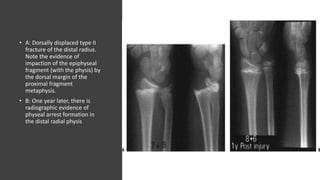

• A: Dorsally displaced type II

fracture of the distal radius.

Note the evidence of

impaction of the epiphyseal

fragment (with the physis) by

the dorsal margin of the

proximal fragment

metaphysis.

• B: One year later, there is

radiographic evidence of

physeal arrest formation in

the distal radial physis